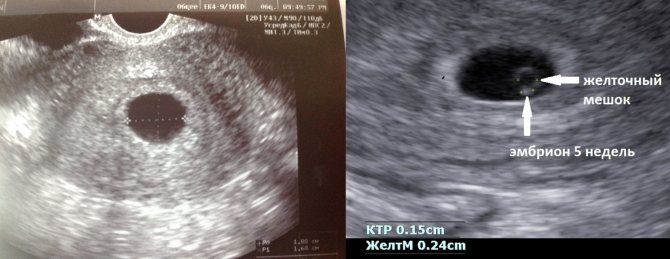

Наиболее достоверно выявить неразвивающуюся беременность можно по результатам ультразвукового исследования при отсутствии сердцебиения плода. Одним из наиболее распространенных вариантов неразвивающейся беременности является анэмбриония, т.е. отсутствие эмбриона в полости плодного яйца после 5-6 недель беременности. При этом плодное яйцо имеет меньшие размеры, чем положено, а эмбрион не визуализируется.

При других вариантах неразвивающейся беременности по данным ультразвукового исследования плодное яйцо по размерам соответствует или отстает в своем развитии, эмбрион может визуализироваться, но без сердцебиения. Нередко может выявляться ретрохориальная гематома, которая представляет собой скопление крови в месте отслойки плодного яйца от стенки матки.